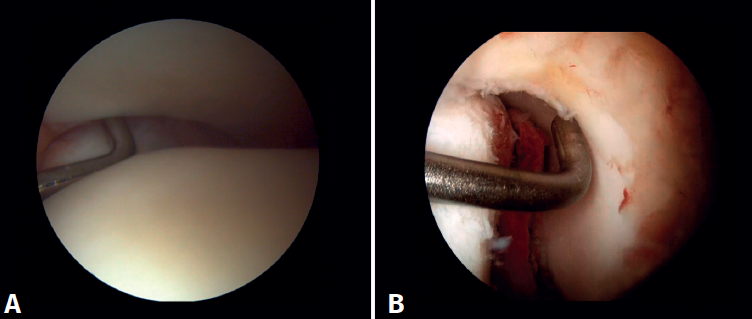

Surgical technique: arthroscopic treatment of acute syndesmosis injuries

The technique should be performed using the conventional anteromedial and anterolateral portals. The anteromedial portal is used for visualization, while the anterolateral portal serves as the working portal. Once the tibiofibular space is visualized, the inflamed synovial component is resected with an arthroscopic shaver to facilitate reduction (Figure 7A). Then, under direct vision, we restore the tibiofibular space, carefully taking into account possible malrotation of the fibula, especially in Maisonneuve type fractures. For fibular reduction we use a Verbrugge clamp, which allows us to correct the rotation. In our experience, once the space has been cleaned and if the position is correct, it is infrequent to have to use a compression clamp between the tibia and fibula.

Once the desired reduction has been achieved, we visually check the position and temporarily fix it using a Kirschner pin.

For definitive fixation, the surgical options range between rigid fixation with screws and dynamic fixation. Screws have been the standard procedure for decades, but involve complications, such as loosening or rupture. Furthermore, some surgeons advocate their removal, with the inherent risk of recurrence of instability(27). Dynamic fixation was designed to overcome some of these problems by allowing a degree of physiological movement of the syndesmosis, facilitating early weight bearing, reducing the risk of rupture, and eliminating the need to remove the implant (Figure 7B).

Grassi et al., in a meta-analysis involving over 300 patients, demonstrated an overall decrease in the relative risk of complications (RR = 0.55, p = 0.003) with dynamic systems(28). Raeder et al., in a randomized trial of 97 patients contrasting screw fixation versus a dynamic system, reported a lower incidence of osteoarthritis with suture buttons of 65% versus 35% (p = 0.009) at 5 years(29). Suture button constructions afford a degree of micro-mobility, mimicking physiological mobility, which can promote ligament healing. Likewise, flexible implants are better able to tolerate an imperfect reduction, as a possible complication, even if arthroscopic control of the joint is performed.

Figure 7. A: debridement of the tibiofibular space; B: stabilization of the syndesmosis using a suspension system.